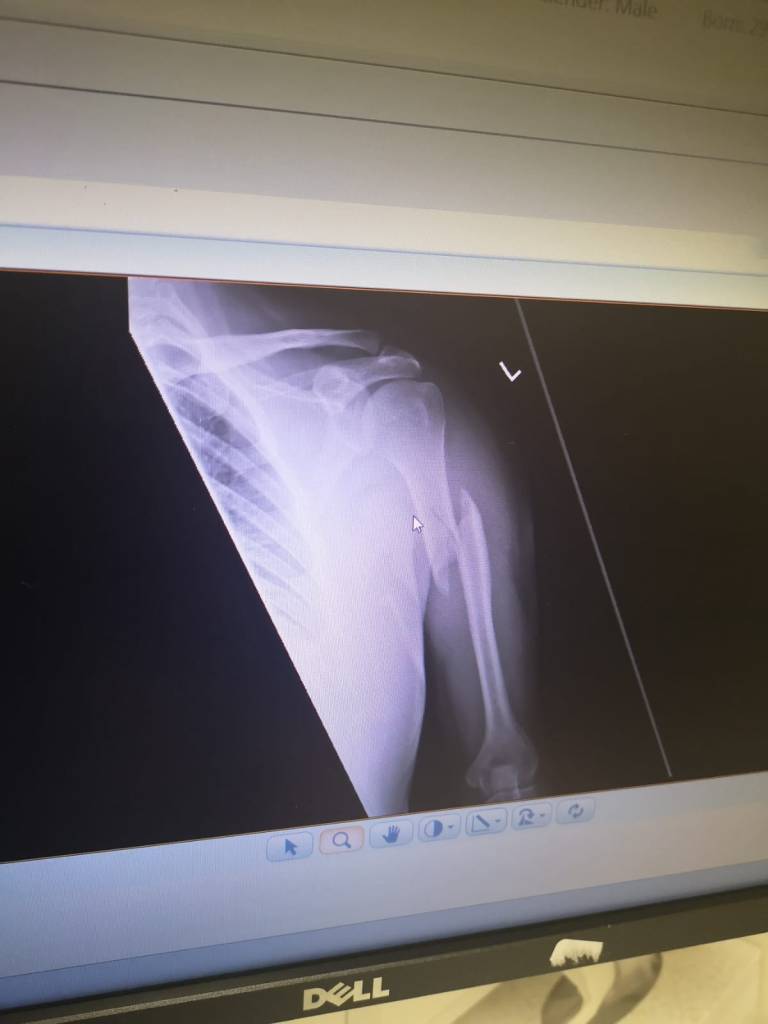

PC Hughes, having broken John’s left arm, realised that it was now necessary to call an ambulance. John was taken for emergency treatment at the Royal Liverpool Hospital. He was assessed at the hospital, and it was established that he had suffered a fracture to the mid shaft of his left humerus, and he was discharged home on the understanding that he would have to return in a few weeks for an operation.

After his terrible injury, John required an operation which involved inserting a metal plate and pins into his left arm to fix the fracture. This left him with a long scar down his arm, which served as a constant reminder of what the Police had done to him, as well as persistent symptoms of stiffness and aching in his arm.

The extent of John’s injury can plainly be seen on the initial x-ray:

After the rejection of John’s complaint, I commenced County Court proceedings on his behalf against the Chief Constable, who would be deemed vicariously liable if John’s allegations against PCs Hughes and Price could be proved in court. I also obtained expert medical evidence proving that John had sustained an oblique/ spiral type fracture to his left humerus which was compatible with a twisting/ bending force being applied to his arm and that, as the fracture was ‘displaced’, this indicated that significant force had been applied.

In response, Merseyside Police argued that the fracture had been caused by John actively resisting PC Hughes’s ‘restraint technique’, as he was ‘taken down’ onto the couch.